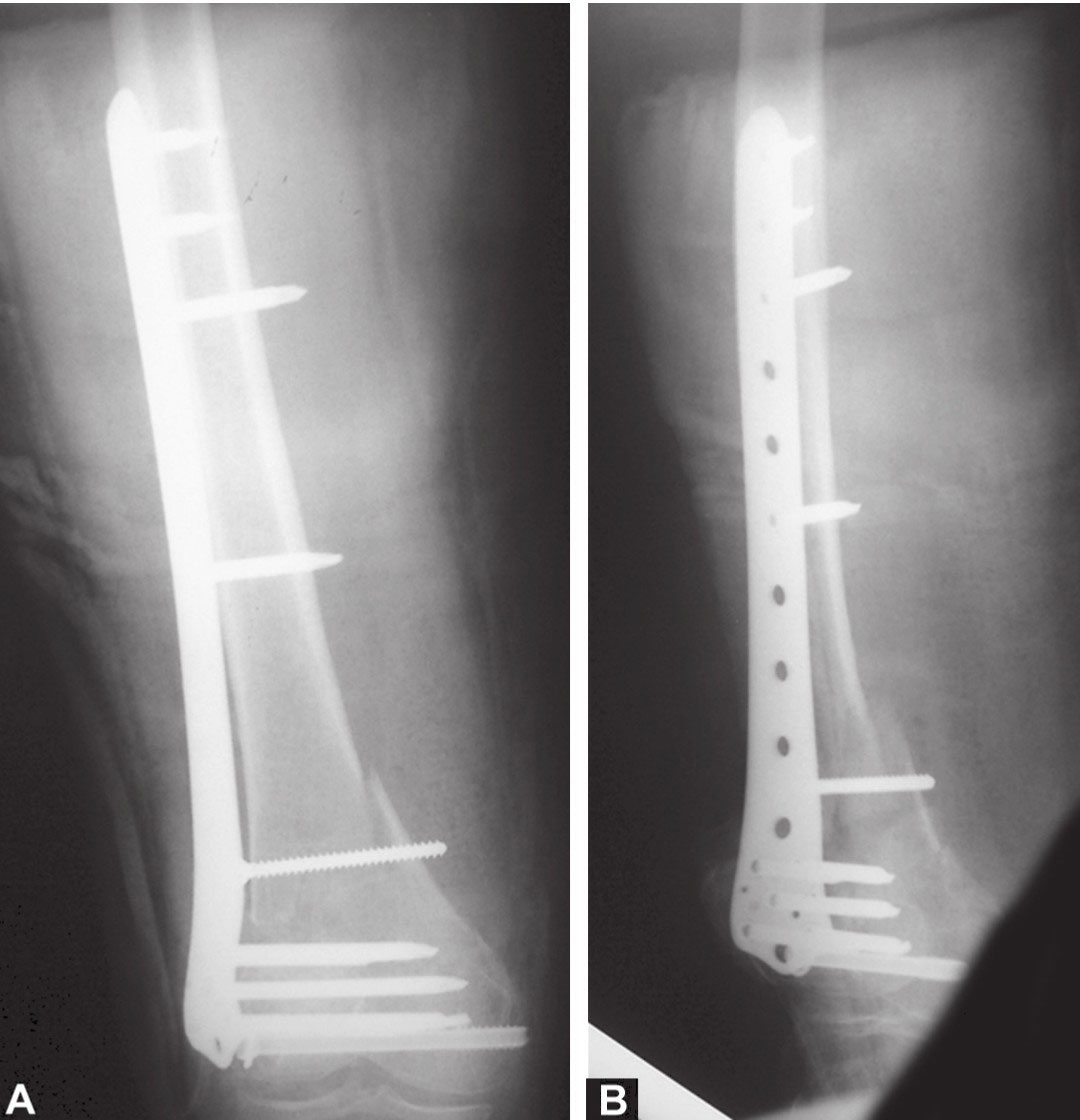

图A和图B术后前后位和侧位X线片显示关节面平整,骨折力线良好

最后,进行了远端股骨锁定钢板内固定。术后,X线片表现满意,感觉无疼痛且能进行良好的关节活动,得到了良好的功能恢复。